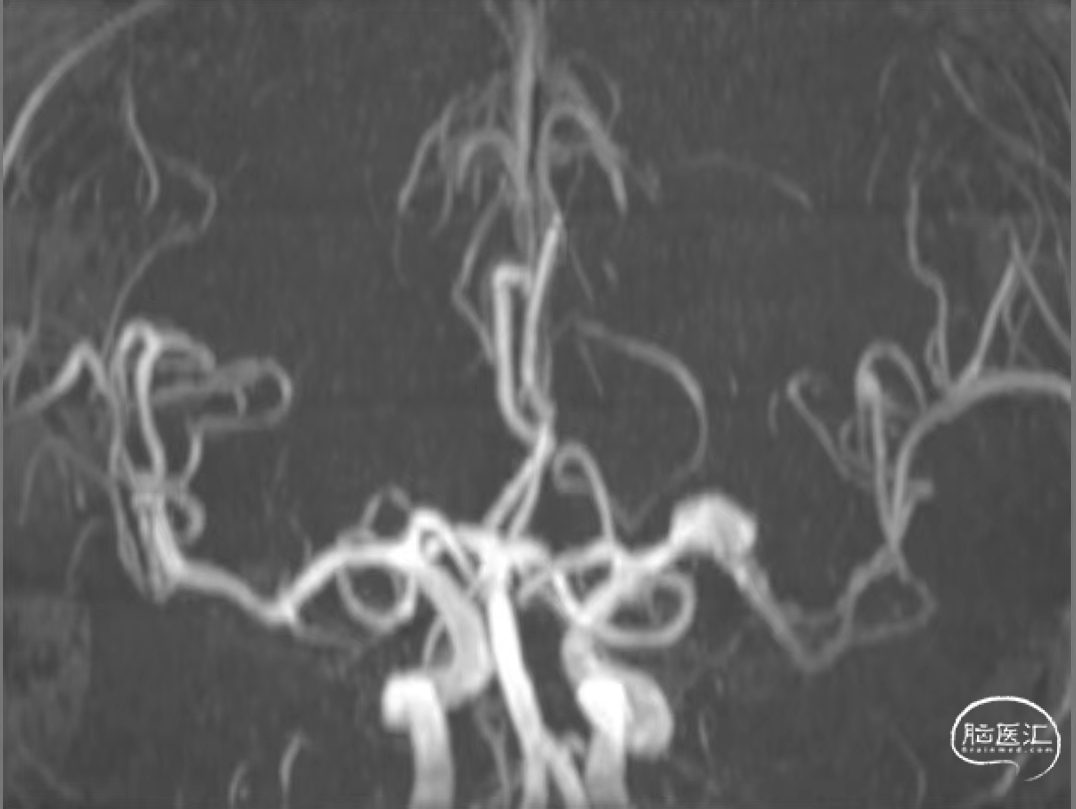

现病史:患者10小时前因突发言语不清伴左上肢力弱,左手持物无力,左下肢活动尚可。病程间无恶心、呕吐等,予以进一步收治入院。入院后完善相关检查,诊断为“急性脑梗死”,行颅脑MRA-TOF提示左侧大脑中动脉M1段瘤样突起,遂予以进一步行脑血管造影检查。

颅脑MRA-TOF造影